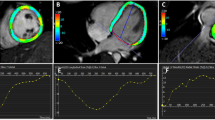

MetS-VLDL induced delayed atrial and ventricular conduction

To evaluate if reduced Cx40 and Cx43 co-exist with slower intra-cardiac conduction velocity, the optical mapping technique was used to image the membrane potential of intact atria and ventricles on ex-vivo perfused hearts21. The membrane potential propagations and the derived conduction velocity of CTL, nVLDL, and msVLDL ex-vivo hearts during rapid atrial pacing (pacing cycle length = 200 ms) were demonstrated in the Fig. 3. The conduction velocity in atria and ventricles were all slower in msVLDL compared with CTL and nVLDL mice (right atria P = 0.0123; left atria, P = 0.0222; right ventricles P = 0.0091; left ventricle, P = 0.0004 by ANOVA analysis).

Atrial and ventricular conduction evaluated by optical mapping in CTL, nVLDL, and msVLDL mice. (a) The right atrial propagations in CTL, nVLDL, and msVLDL during rapid atrial pacing (pacing cycle length = 200 ms) were demonstrated in the isochronal map. The white asterisk indicates the pacing site. (b) The conduction velocity was compared among CTL, nVLDL, and msVLDL groups. The conduction velocity in RA, RV and LV were all slower in msVLDL than in CTL and nVLDL mice. Although the conduction velocity in LA is slower in msVLDL than in nVLDL mice, there is no difference in conduction velocity comparing LA in msVLDL than CLT group. $P < 0.05 compared with CTL. #P < 0.05 compared with nVLDL.